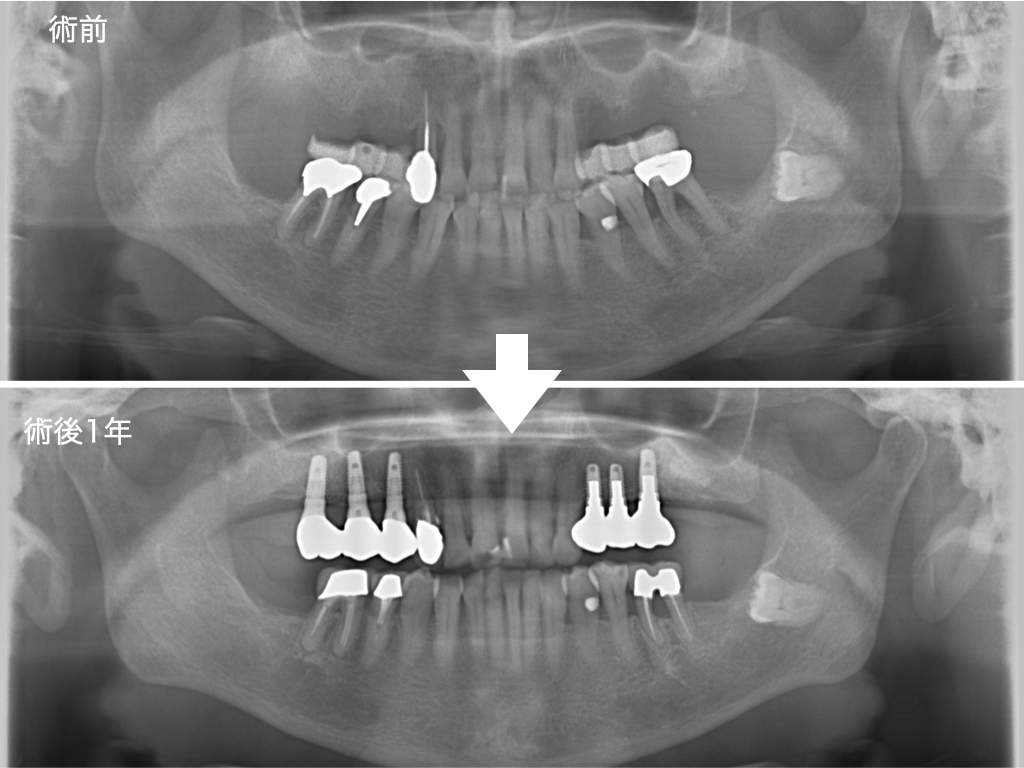

本日は、歯周病により上顎の奥歯を失い、入れ歯でお困りだった60代女性の患者さまにインプラント治療を行った症例をご紹介いたします。

上顎の左右臼歯部(奥歯)に3本ずつ、合計6本のインプラントを埋入し、奥歯の強固な噛み合わせを構築しました。

本症例のように「前歯しか残っていない状態」において、よく噛める入れ歯を作製することは力学的に非常に困難です。さらに、入れ歯のままの状態でいると残存している前歯に過度な負担がかかり、連鎖的に前歯まで悪くなってしまうリスクが高まります。

このようなケースでは、インプラント治療によって奥歯に安定した噛み合わせを確立することで前歯への負担を大幅に軽減し、口腔内全体の健康を長期的に維持することが可能となります。

歯周病治療を行った後、上顎両側臼歯部に合計6本のインプラント埋入を行いました。 現在は、定期的なメインテナンスに移行しております。